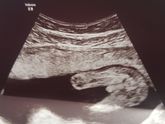

Не дождалась второго скрининга и сегодня мы с мужем пошли на узи. Нам 16 недель и 3 дня, по размерам соответствуем 16 н. 5 д. Весим 200 грамм)) Развиваемся хорошо) Нам сказали пол, у нас будет сынок! В 13 недель ходили на первый скрининг, предположили … Читать далее